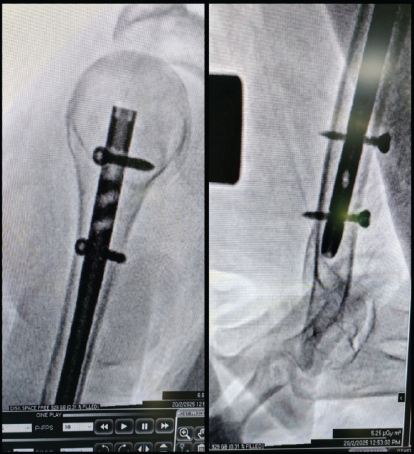

Reaming was carried out slowly and with low torque, to minimize the risk of cortical blowout in fragile bone. A nail of suitable length and diameter was introduced and its proximal end sunk flush with the articular surface, preventing impingement. Proximal fixation was secured with two divergent locking screws (Fig. 3). At the distal end, screws were placed in a single plane, a conscious choice to balance stability against the risk of excessive cortical perforation (Fig. 3).

Figure 3: C-arm images showing the proximal and distal locking.